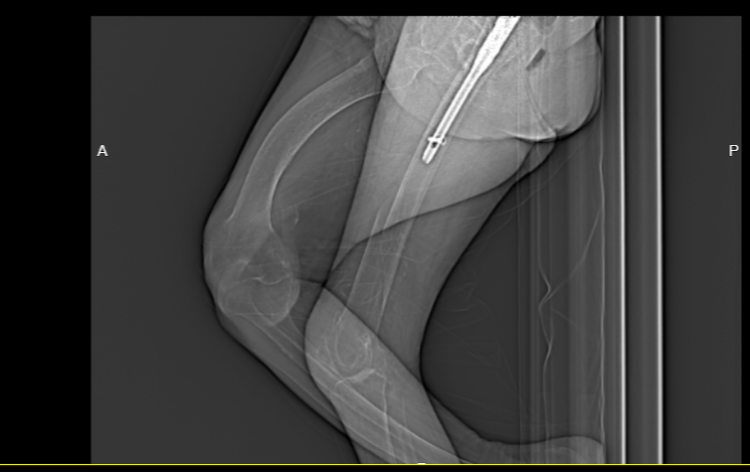

入院后,谢桥医院骨科团队一边为李奶奶完善相关检查等治疗,一边进行多学科会诊紧急讨论。考虑到李奶奶是高龄骨折,同时在此之前已经进行过一次关节置换,针对这些手术难点,以及术中可能出现的突发情况,术前谢桥医院骨科团队经过反复讨论,并与其家属沟通后,最终确定了严密的手术计划和全面的治疗方案,决定为李奶奶施行“右侧股骨干骨折切开复位内固定术”。目的便是为了提高术后康复效果,极大程度减少并发症。

术后,李奶奶的病情平稳,恢复良好。谢桥医院骨科的护理团队悉心为李奶奶进行了专业护理,指导其做好术后各阶段的康复训练,目前李奶奶已经平安出院。